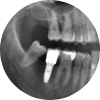

상실된 치아를 위한 선택, 임플란트

Dental Implant

영구치는 한번 빠지면 다시 나지 않습니다. 틀니와 브릿지 등 손실된 치아의 기능을 보충하는 보철물들이 있으나

많은 단점이 있어 사용에 불편합니다. 임플란트를 통해 새로운 내 치아를 탄생시켜 보세요.

유치 후에 영구치가 있다면 영구치 후에는 내 인생 세 번째 치아, 임플란트가 있습니다.